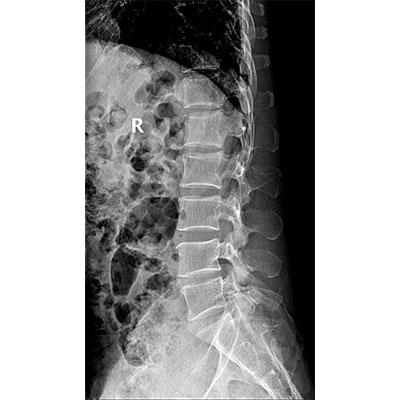

● 采用自主研發(fā)的技術,在保證優(yōu)質圖像的前提下,大大降低X射線劑量,用心呵護醫(yī)護工作者及患者的健康。

● 短曝光時間,便于老年人、兒童、殘疾人進行臨床拍攝。避免這類群體因不能有效控制身體運動等因素造成的運動偽影,提高攝片質量及效率。